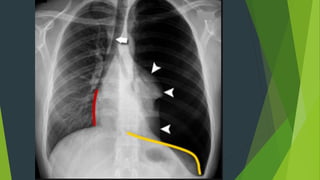

Tràn dịch màng phổi tự do

 Hình ảnh mờ đậm thuần

nhất , không có hình ảnh

nhu mô phổi.

 Mất góc sườn hoành

 Có đường cong Damoiseau

TDMP lượng vừa ( Đường

cong Damoiseau

TDMP tự do lượng nhiều

Tràn khí màng phổi

 Phổi bên tràn khí sáng hơn bình

thường, bên trong vùng sáng

không có hình ảnh nhu mô phổi

 Nhu mô phổi bị ép xẹp về phía

rốn phổi

 Cơ hoành bị đẩy xuống thấp

 Tim và khí quản bị đẩy về phía

đối diện